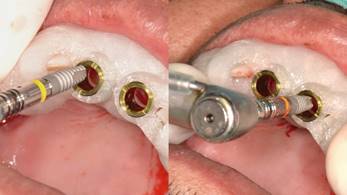

Posteriormente se realizó una impresión de alginato y vaciado en yeso del maxilar, se eliminaron mecánicamente ambos incisivos centrales. Este modelo se digitalizó con un escáner extraoral (3Shape, Trios) y se obtuvo un archivo STL. Luego con esto datos se hizo una coincidencia digital entre el CBCT y el archivo STL, utilizando el software BlueSky plan, (BlueSky bio). Se planificaron dos implantes cónicos de conexión interna de 3.8 x12 mm (Biohorizons), separados de la parte vestibular de las raíces y asegurando su correcto posicionamiento implantario (Img 1). Luego se diseñó una guía quirúrgica en el mismo software, exportada e impresa en ácido poliláctico (PLA) por una impresora de tecnología de deposición de material fundido (FDM) (Duplicator 7, Wanhao, China). Después de la anestesia local, se extrajo la porción coronal de ambos dientes fracturados, luego las partes apicales restantes se dividieron mesio-distalmente con una fresa de diamante de alta velocidad dejando dos porciones. Se retiró la parte palatina y se conservaron 5 mm de la pared vestibular radicular, posteriormente se instaló la guía quirúrgica en posición (Fig 2 y 3).

El protocolo de fresado llegó a los 21 mm de profundidad y a la fresa de 3.2 mm de diámetro. Ambos implantes alcanzaron 40 N de torque, todo bajo un protocolo de cirugía e inserción guiada estricta de implantes (Fig. 4).

Después de la cirugía, ambas coronas naturales se adaptaron para ajustarse a un pilar temporal de titanio. Utilizando el adhesivo Universal (3M ESPE) y cementadas con resina fluida (A2 3M ESPE), siguiendo el protocolo de adhesión del fabricante, se confeccionaron las coronas provisionales, las que fueron instaladas como provisorios inmediatos en los implantes en boca, fue citado a control post operatorio, donde se tomó Radiografía panorámica (Img 2). Dándose de alta 21 días post intervención. Se hizo seguimientos a los seis y doce meses posteriores al alta.